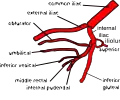

BranchesIliolumbar artery, lateral sacral artery, superior gluteal artery, inferior gluteal artery, middle rectal artery, uterine artery, obturator artery, inferior vesical artery, superior vesical artery, obliterated umbilical artery, internal pudendal artery, vaginal artery

The arrangement of branches of the internal iliac artery is extremely variable.[3] Typically, the artery divides into an anterior division and a posterior division, with the posterior division giving rise to the superior gluteal, iliolumbar, and lateral sacral arteries. The rest usually arise from the anterior division. Because it is variable, an artery may not be a direct branch, but instead might arise off a direct branch.

The following are the branches of internal iliac artery:

Right (distal from spectator) internal iliac artery and branches, except for iliolumbar artery, umbilical artery, uterine artery/deferential artery and vaginal artery/inferior vesical artery.